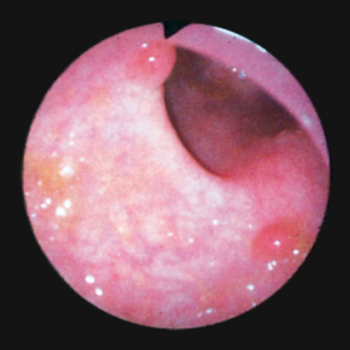

This slide show features a CT image, and pathology images of gastrointestinal stromal tumors (GISTs) arising in the stomach using H&E, CD34, and c-Kit staining.